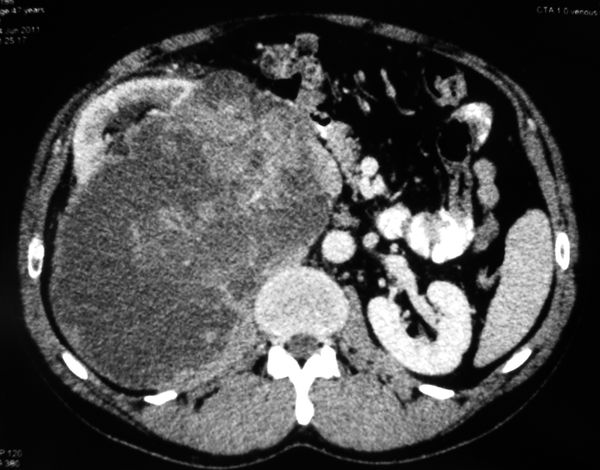

Огромная опухоль правой почки

Гигантская опухоль правой почки. Экстримальная нефрэктомия.